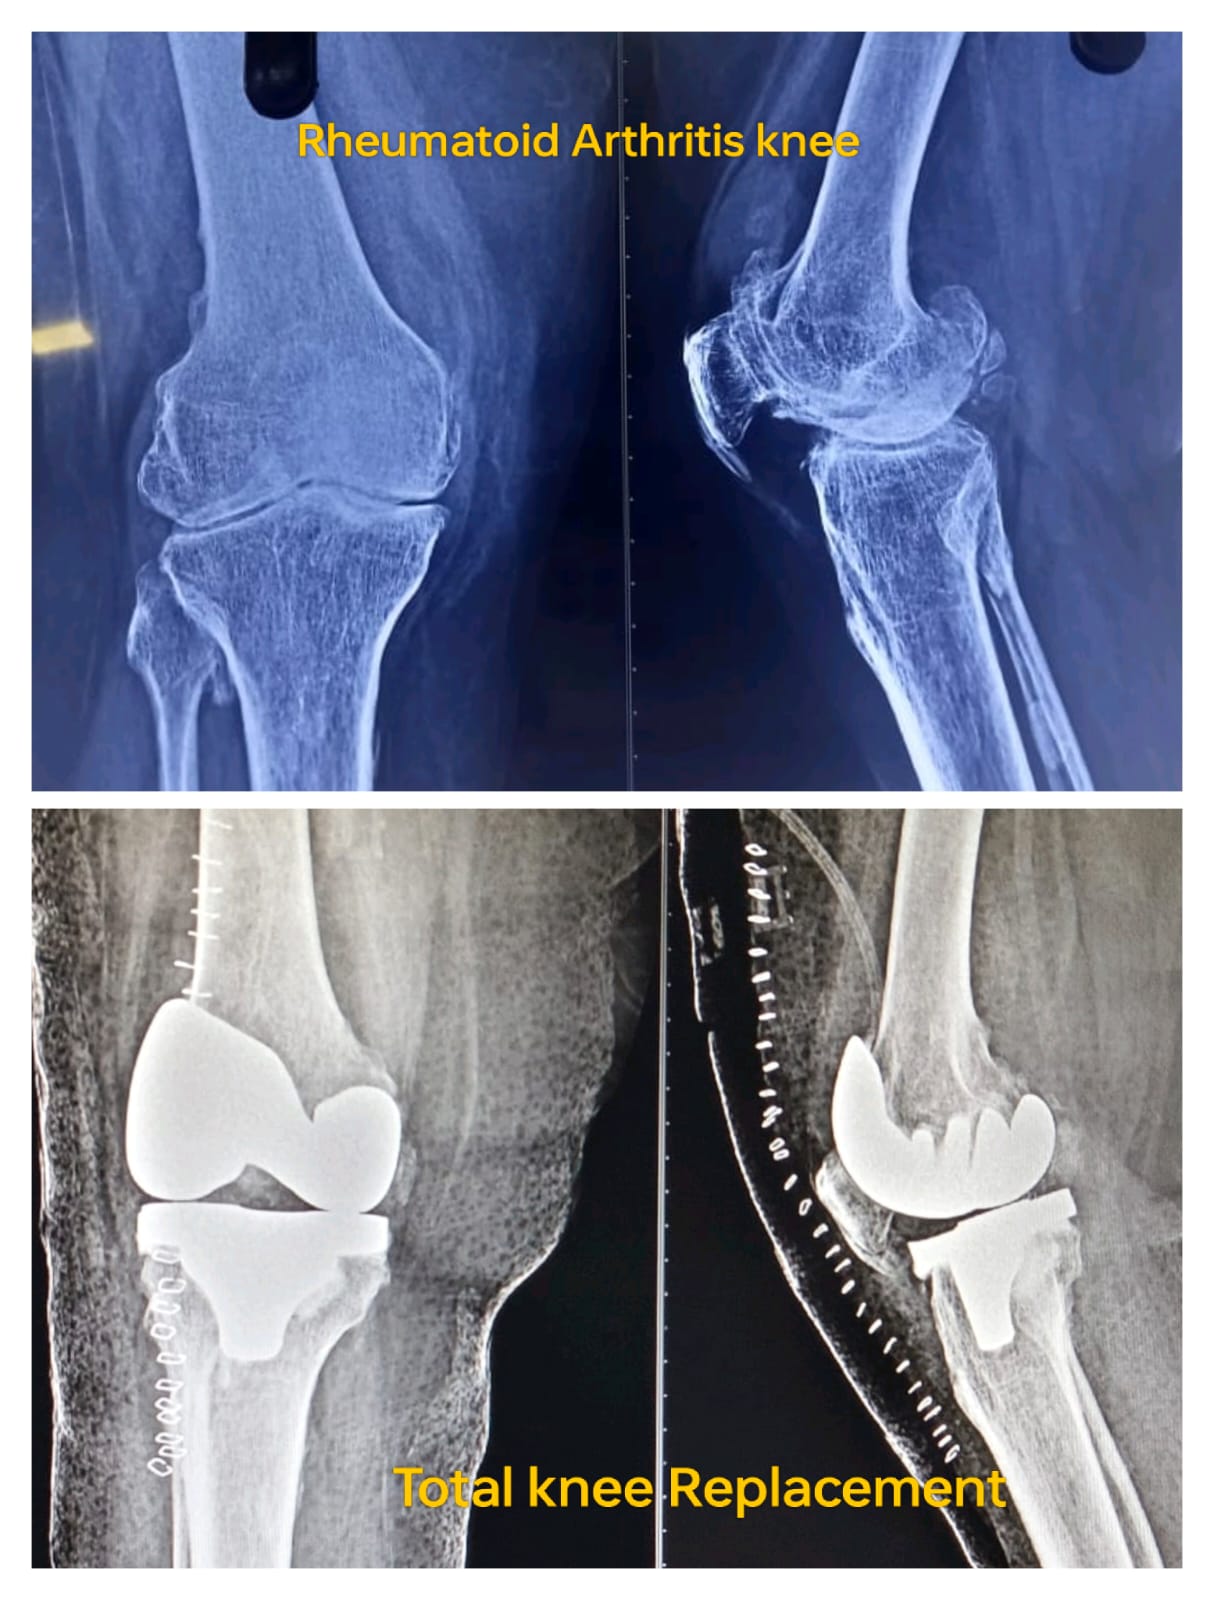

Knee Arthroplasty is a surgical procedure where I replace a damaged knee joint with an artificial implant to restore function and relieve pain. This procedure is most suitable for patients with severe osteoarthritis, rheumatoid arthritis, post-traumatic arthritis, or cartilage damage that limits mobility. By replacing only the affected parts (partial knee replacement) or the entire joint (total knee replacement), I can tailor the surgery to each patient’s condition.

During knee replacement surgery, I remove the damaged cartilage and bone from the knee joint and replace it with a durable artificial implant. I use precise surgical techniques to ensure accurate alignment, stability, and joint function. Depending on the patient’s needs, I may perform total knee replacement or partial knee replacement. Each procedure is carefully planned and executed to maximize outcomes and minimize recovery time.

Before surgery, I perform a detailed evaluation including physical examination, blood tests, and imaging like X-rays or MRI to understand the knee condition. Patients receive pre-operative instructions on fasting, medications, and arranging support at home during recovery. Proper preparation helps ensure a smooth, safe procedure with minimal complications.

- Imaging Tests: X-rays, MRI for surgical planning